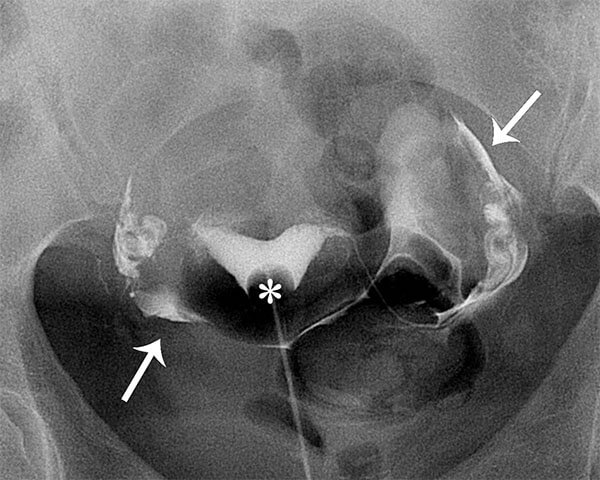

Fluoroscopic hysterosalpingography (HSG) is an x-ray examination of the uterus and fallopian tubes using a special form of low dose x-ray called fluoroscopy and iodinated contrast material (a liquid containing iodine that is visible to x-rays).

The most common reason for an HSG is to evaluate subfertility/infertility or repeat miscarriages. The main purpose of the exam is to evaluate for blockages of the fallopian tubes, but the exam also provides information about the uterine cavity, such as shape and presence of scarring, and whether there may be adhesions or scarring in the pelvis.

- The radiologist will insert a speculum into the vagina, clean the cervix and insert a catheter into the uterus. The speculum is then removed, and contrast material infused through the catheter while images are taken.